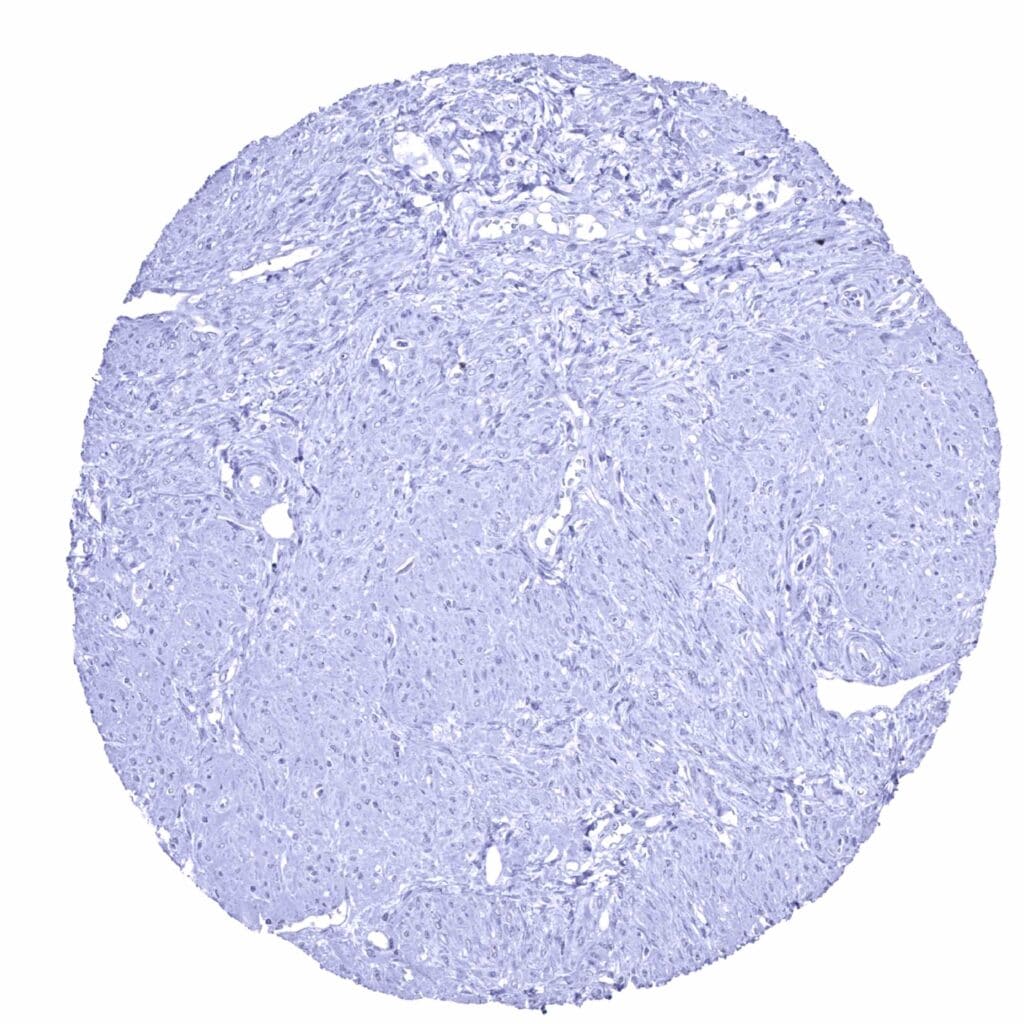

Uterus, ectocervix